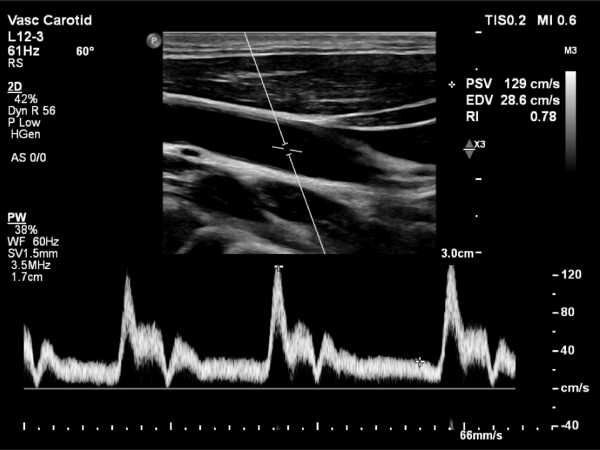

Dr. Ghalichi personally performs carotid artery ultrasounds using the state-of-the-art Philips EPIQ Elite (Netherlands) system equipped with AI tools.

• Operator-Dependent Expertise: Benefit from Dr. Ghalichi's specialized skills in conducting and interpreting the ultrasound.

• Intima-Media Thickness (IMT) Measurement: Accurate assessment of the thickness of your arterial walls.

• Radiation-Free Imaging: Safe and painless procedure with no exposure to radiation.

• Trackable Results: Monitor changes in IMT over time to evaluate the effectiveness of treatment strategies.

Carotid Artery Ultrasound Image 1 Carotid Artery Ultrasound Image 2